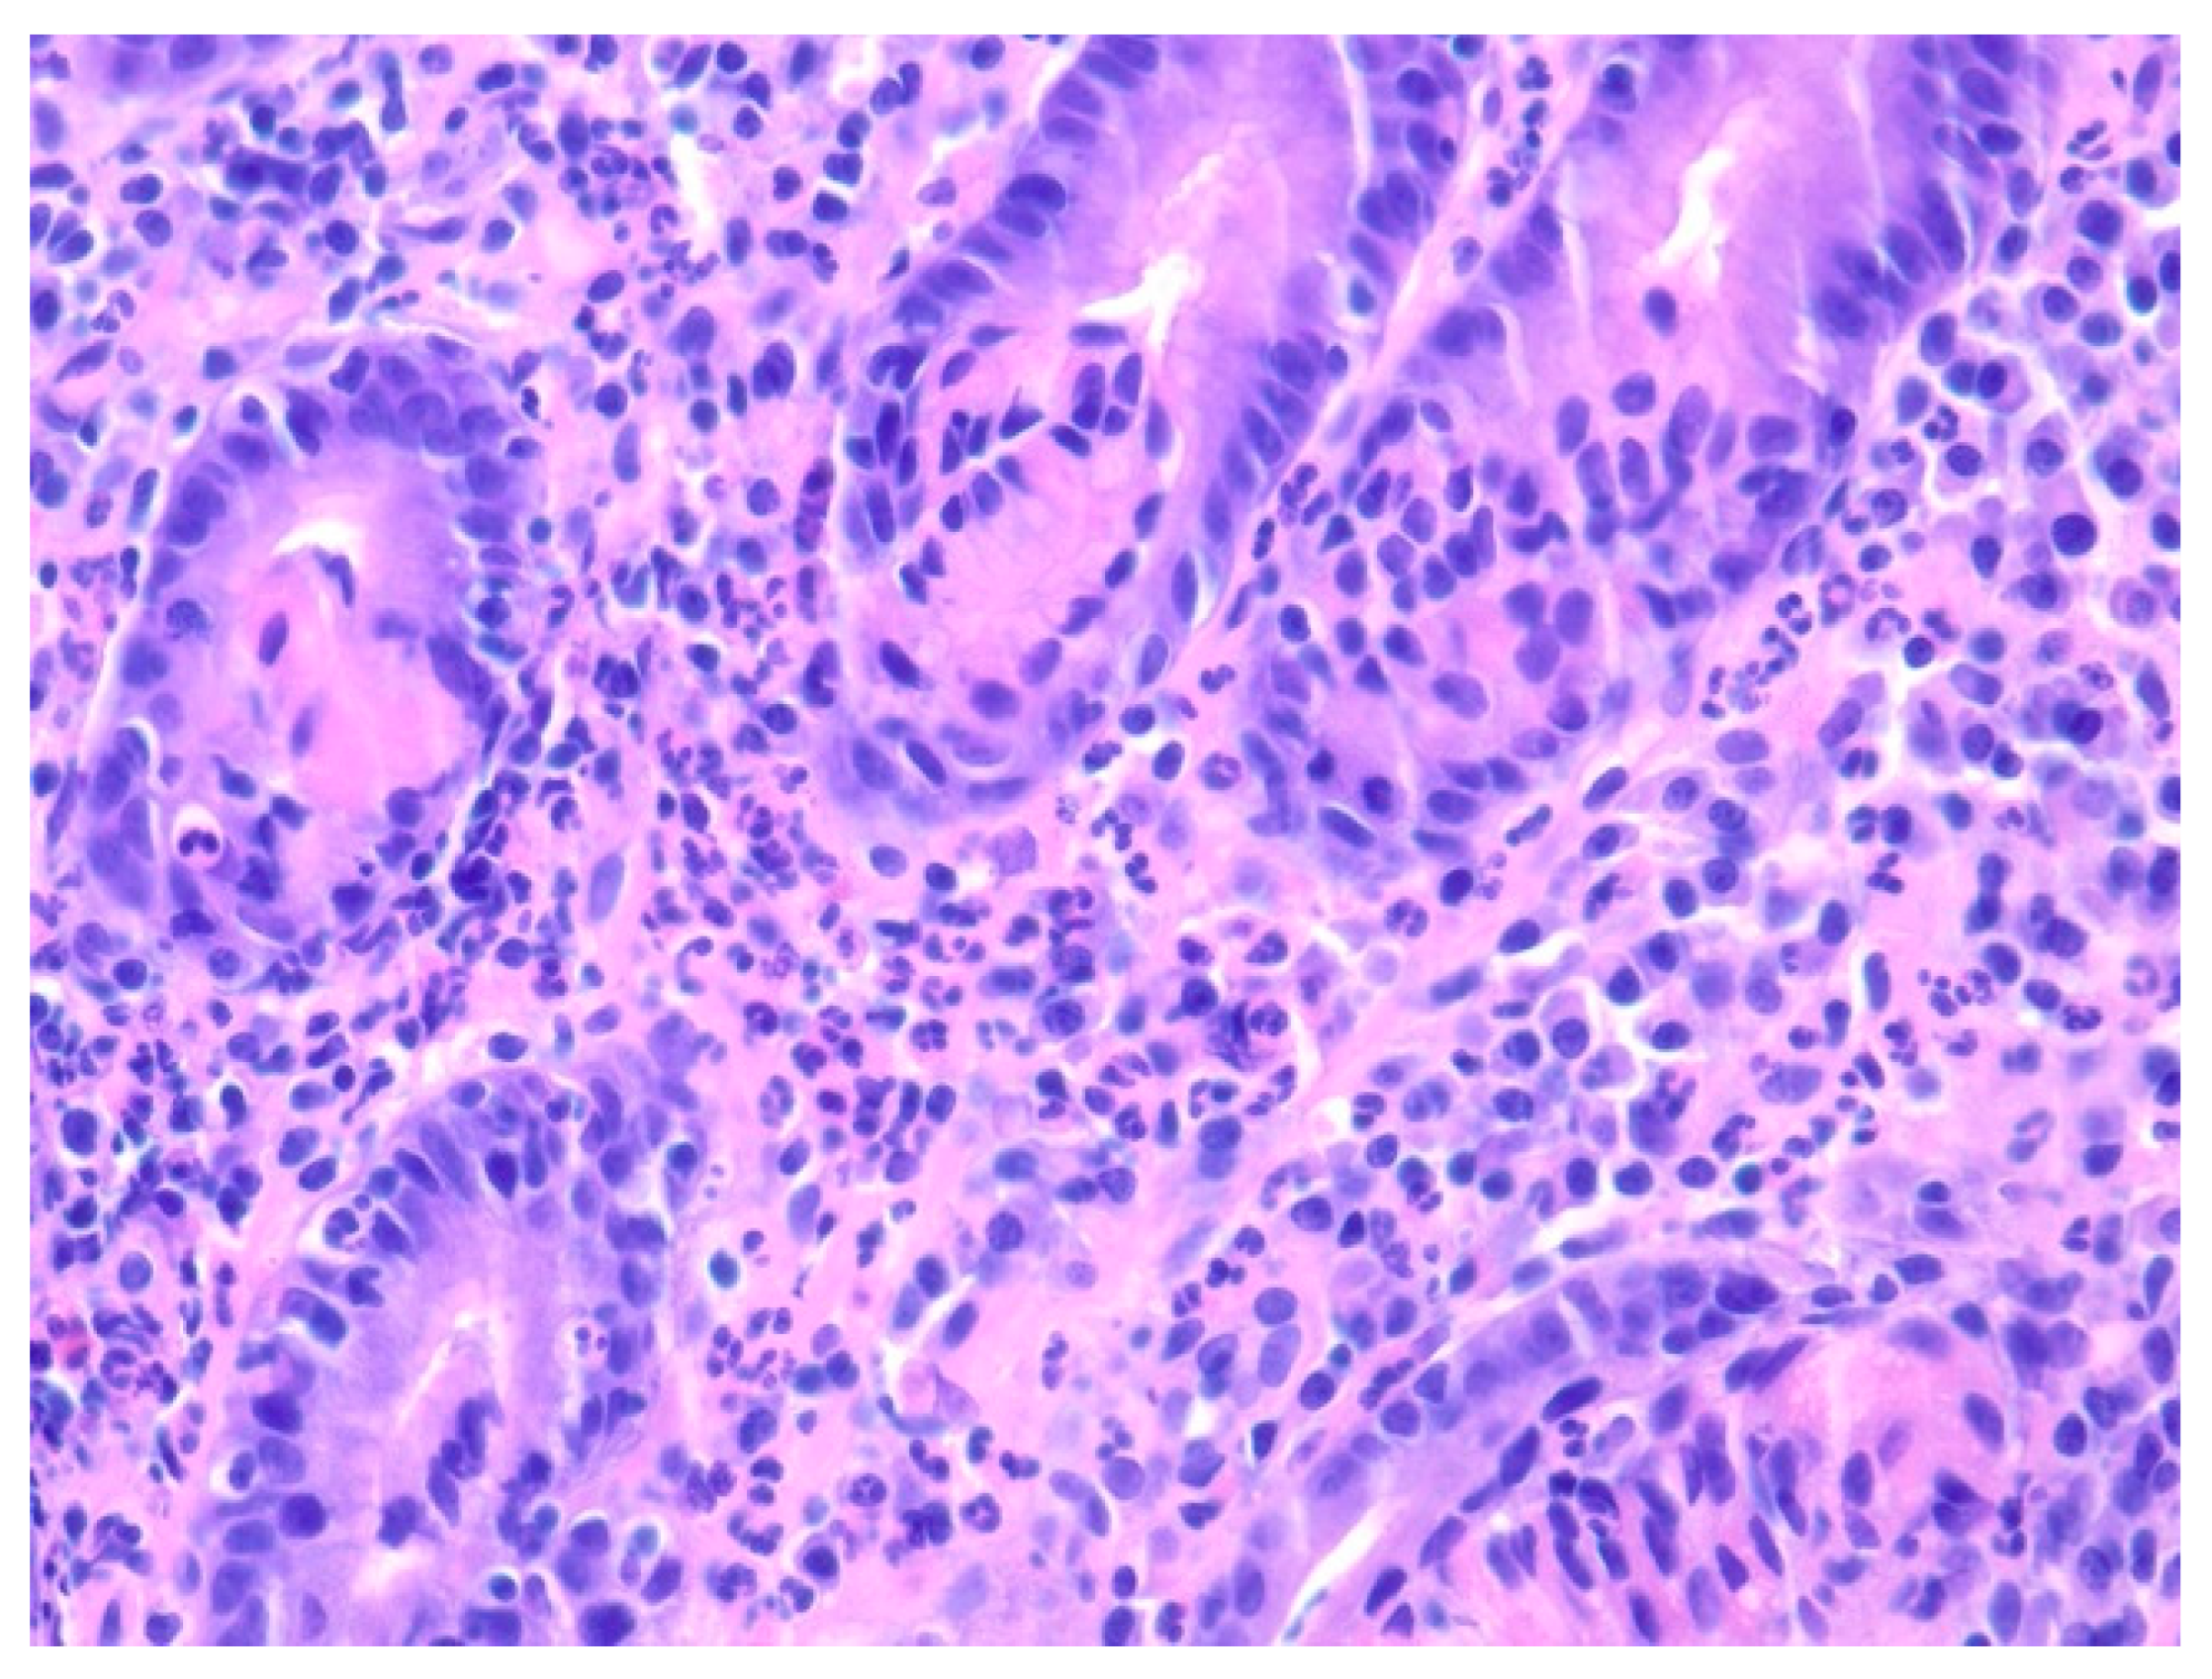

| 1 | F | 66 | Skin | Fundus, cardia, and body | Polypoid lesions with superficial ulcers | Esophagus, duodenum, mediastinum, cervical soft tissue, pancreas | Metastatic malignant melanoma | Radiotherapy and immunotherapy | Comfort care and death 5 days after EGD diagnosis of metastasis |

| 2 | M | 84 | Lymphoid | Fundus and cardia | Ulcerated and necrotic mass | Liver, urinary bladder | Diffuse large B-cell lymphoma | None | Death in 2 months after EGD diagnosis of metastasis |

| 3 | F | 35 | Lung | Fundus | Fungating mass | Esophagus, mediastinum | Large-cell neuroendocrine carcinoma | Chemotherapy-carboplatin/ etoposide | Death 1 month after EGD diagnosis of metastasis |

| 4 | F | 73 | Kidney | Fundus and body | Multiple large friable masses | Liver and lungs | Clear cell renal carcinoma | Nephrectomy, chemotherapy, immunotherapy (Axitinib) | Death 10 days after EGD diagnosis of metastasis |

| 5 | M | 76 | Lung | Body | Cratered ulcers | Liver, bone and adrenals | Small cell carcinoma (poorly differentiated neuroendocrine Ca) | None | Death 7 days after EGD diagnosis of metastasis |

| 6 | M | 61 | Lymphoid | Unknown | Clean based ulcer | None | Marginal zone lymphoma | Rituximab, Zanubrutinib, umbrasilib. OCHOP regimen currently | Progressive disease per latest scans despite therapy |